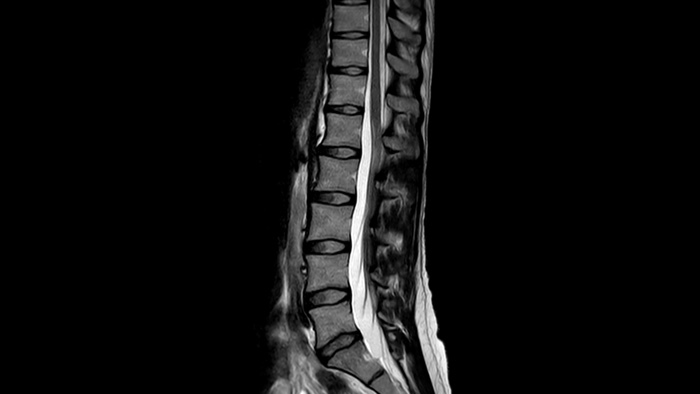

SmartSpeed Штучний інтелект SmartSpeed дозволяє скоротити час сканування до 65% з такою ж або вищою якістю зображення

Діагностична точність Розширте свої можливості візуалізації в усіх клінічних областях. Дізнайтеся, які переваги отримують ваші колеги.

Швидкість і& комфорт Зниження необхідності затримки дихання на 40% без втрати якості зображення4.